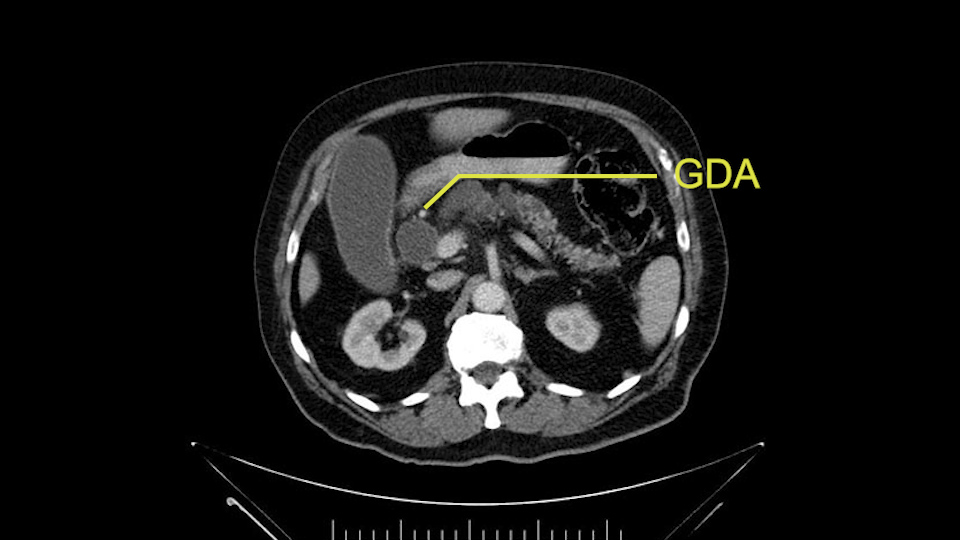

The other thing I look at is the gastroepeiploic arcade- which is this thing here- which is where the gastroepeiploic vein joins the portal vein. I call it the gateway to the neck of the pancreas because you pretty much have to divide it to get to the neck. The middle colic vein usually drains either into it or nearby. I think we’re seeing it here. Again,that can be divided and I usually divide those two and it helps me get under the neck. Again, there’s no issues here with the tumor so it’s nice from that perspective. If I was concerned about the vein, which I’m not here, I would go to the coronal view. It’s a nice way to look at the vein on just a couple of cuts and you can see a beautiful view of it here. There’s the portal vein, there’s the head of the pancreas. There’s the tumor. It’s a little closer here than it looks on the other one. I doubt it’s involved. If it’s touching, it may not be invading it but even if it was, it's a short segment. Anyways, there’s the SMV there’s the splenic vein, and everything looks good. You can see the stent. I ignore the stent. It’s the most dramatic looking thing in the picture but it’s actually the least important.

The gastroduodenal artery, a major artery that we have to divide, along with some pancreatoduodenal arteries, may have atherosclerotic changes so they would have to be handled with care, when I attempt what I think would be a pylorus-preserving pancreatoduodenectomy would be the plan. In some cases, I might make an intraoperative change and do a partial antrectomy or a pylorus-resecting Whipple, should the need arise for technical reasons but not because of the size of the tumor.

The other slowing down moment would be the gastroduodenal artery. Confirming that the gastroduodenal artery is not a dominant artery supplying blood to the liver. Liver failure is something which we don’t want due to altered blood supply to the liver or hampered arterial blood supply to the liver. So I would dissect out the hepatic artery, the left and right branches very clearly. Put a bulldog clamp on the gastroduodenal artery, make sure that the perfusion of the liver is excellent on the right and left side, and then divide the gastroduodenal artery. I would avoid using crushing instruments or crushing clamps on the gastroduodenal artery because they have a tendency to shatter in patients who are old with friable vessels so you have to be careful and tackle it with the help of a 5-0 or a 6-0 prolene sutures. In younger patients, I would just apply clips and move on when it comes to dividing the gastroduodenal artery.

First, the stenosis of the celiac trunk, which can be caused by arteriosclerosis, especially in a patient who is 83, or in patients who have arcuate ligament; we do see it, sometimes in much younger patients. In those cases, it may be that the circulation of the hepatic artery comes entirely from the gastroduodenal artery and its anastomoses, through the pancreaticoduodenal arteries, coming from the superior mesenteric artery. This means that before the gastroduodenal artery is ligated, we first clamp and wait 30 seconds to a minute, to feel and check the arterial inflow to the liver. If the pulse is diminished or there is a complete absence of the pulse, the surgery should be modified or probably a pancreatoduodenectomy cannot be done, because of the risk - when ligating the gastroduodenal artery - of causing fulminant hepatic ischemia postoperatively.

La primera que mencionamos, la estenosis del tronco celíaco, que puede ser causada por arterioesclerosis, especialmente en este paciente de 83 años, ó por pacientes que tienen ligamento arcuato; ese sí lo vemos, a veces, en pacientes mucho más jóvenes. En esos casos, puede resultar que la circulación de la arteria hepática provenga completamente a través de la arteria gastroduodenal y sus anastomosis, por las arterias pancreaticoduodenales, provenientes de la mesentérica superior.

Esto quiere decir la precaución que tenemos, es que -antes de ligar la arteria gastroduodenal- durante la pancreatoduodenectomía, hacemos un clampeo, esperamos 30 segundos o un minuto, y palpamos y vemos el pulso hepático. Si el pulso hepático se disminuye o hay ausencia completa del pulso, debe modificarse la cirugía; probablemente no se pueda hacer la Pancreatoduodenectomía, por el riesgo -al ligar la arteria gastroduodenal- de causar una isquemia hepática fulminante en el postoperatorio.

I am a believer in pylorus preservation. And in this case I see no reason why that wouldn't be possible. Mobilize the duodenum, divide the gastroepiploic vessels and divide the duodenum. I try to divide it with a linear stapler about four centimeters from the pylorus to have adequate length for my GI anastomosis. This facilitates exposure of the head neck of the pancreas. I find the gastroduodenal artery. This patient has normal arterial anatomy. Always on every preoperative CT scan I look to see if there is a replaced right hepatic. In this case I did not see one. Regardless of how confident I am I always look carefully for variant anatomy. I always do a clamp test on the GDA before ligation. I doubly ligate the GDA with not just a tie but a suture ligature because of the risk of GDA blowout in patients with a leak.